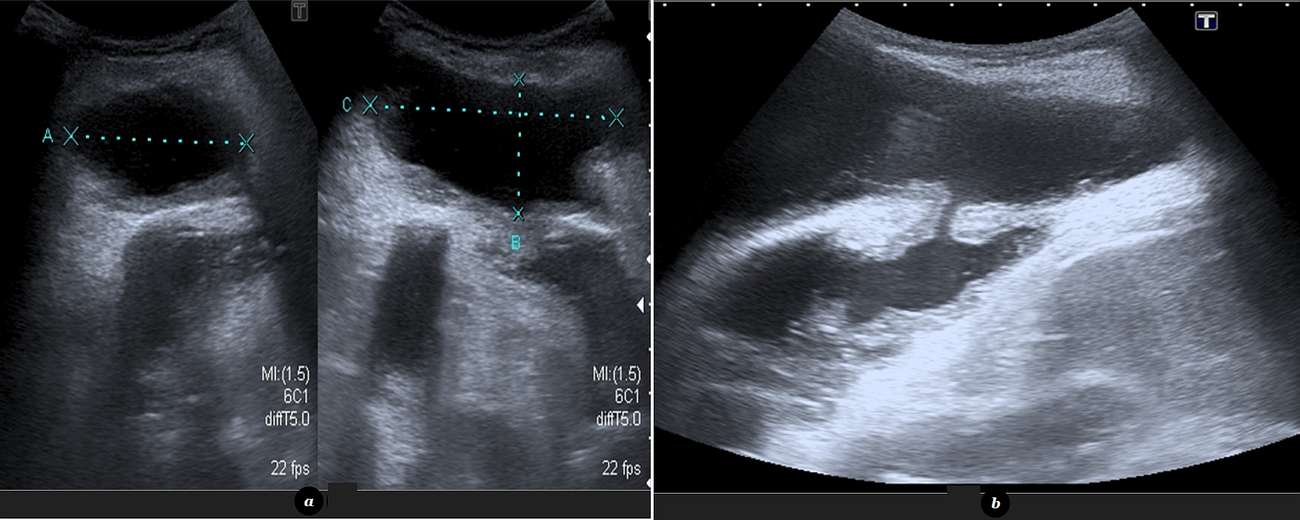

Imaging findings were further investigated with contrast-enhanced computed tomography (CT) imaging. CT revealed a loculated left pleural effusion with thickened, contrast-enhanced and partially calcified pleural surfaces that communicated with an organized, subcutaneous chest-wall fluid collection.

While chest radiography can suggest the diagnosis, demonstrating a loculated pleural effusion in a patient with past history of pulmonary tuberculosis presenting with an anterior chest wall mass, the definitive imaging findings are usually seen with CT. Contrast-enhanced CT clearly demonstrates the existence of a communication between the empyema (i.e.: a loculated pleural effusion with thickened and enhancing pleural surfaces) and a well-deliniated chest wall fluid collection with thickened and enhancing walls, representing an abscess [6]. US and CT can also aid in the therapeutic process, guiding the thoracostomy necessary to drain the pleural cavity.